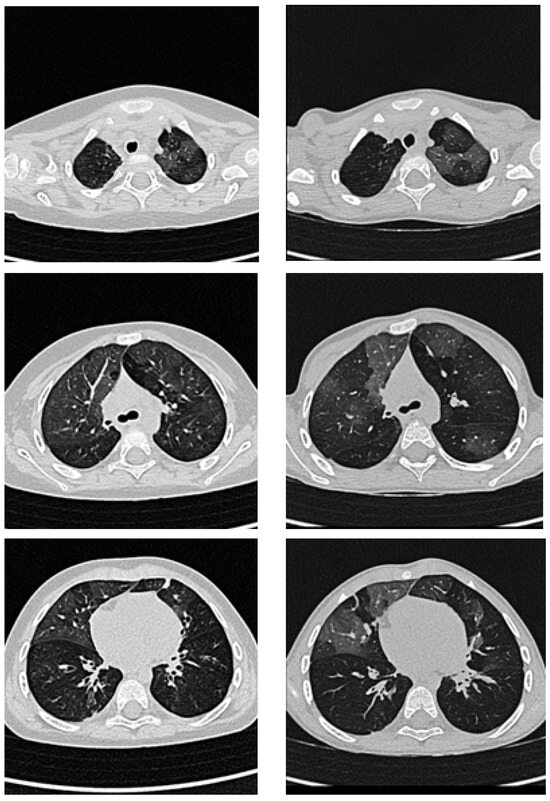

A Question of Dose? Ultra-Low Dose Chest CT on Photon-Counting CT in People with Cystic Fibrosis

Objective: Chest computed tomography (CT) is a key component of the diagnostic assessment of people with cystic fibrosis (PwCF) and is increasingly replacing chest radiography. Due to improvements in life expectancy, radiation exposure has become a growing concern in PwCF. Photon-counting CT (PCCT) [...] Read more.

Objective: Chest computed tomography (CT) is a key component of the diagnostic assessment of people with cystic fibrosis (PwCF) and is increasingly replacing chest radiography. Due to improvements in life expectancy, radiation exposure has become a growing concern in PwCF. Photon-counting CT (PCCT) has the potential to reduce the risk of radiation-induced malignancies while maintaining diagnostic accuracy. This study aimed to compare the radiation dose and image quality of low-dose high-resolution (LD-HR) and ultra-low-dose high-resolution (ULD-HR) CT protocols using PCCT in PwCF. Methods: This retrospective study included 72 PwCF, with 36 undergoing a LD-HR chest CT protocol and 36 receiving an ULD-HR protocol on a PCCT. The radiation dose and image quality were assessed by comparing the effective dose and signal-to-noise ratio (SNR). Three blinded radiologists evaluated the overall image quality, sharpness, noise, and assessability of the bronchi, bronchial wall thickening, and bronchiolitis using a five-point Likert scale. Results: The ULD-HR PCCT protocol reduced radiation exposure by approximately 65% compared with the LD-HR PCCT protocol (median effective dose: 0.19 vs. 0.55 mSv, p < 0.001). While LD-HR images were consistently rated higher than ULD-HR images (p < 0.001), both protocols maintained diagnostic significance (median image quality rating of “4-good”). The average SNR of the lung parenchyma was significantly lower with ULD-HR PCCT compared to LD-HR PCCT (p < 0.001). Conclusions: ULD-HR PCCT significantly reduced radiation exposure while maintaining good diagnostic image quality in PwCF. The effective dose of ULD-HR PCCT is only twice that of a two-plane chest X-ray, making it a viable low-radiation alternative for routine imaging in PwCF. Full article